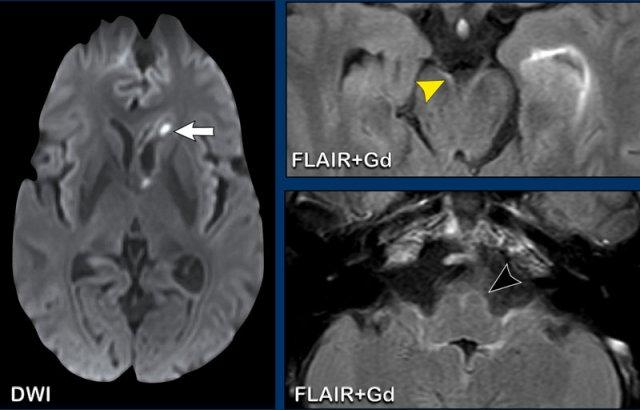

Các hình ảnh này của bệnh nhân nam 62 tuổi, nhập viện với các triệu chứng đau đầu, sốt và li bì.

Hình ảnh

Trên chuỗi xung FLAIR có tiêm thuốc tương phản từ, quan sát thấy lớp lót tăng tín hiệu dọc theo thành não thất bên trái, biểu hiện ngấm thuốc mỏng, rõ hơn so với hình ảnh trên chuỗi xung T1W có tiêm thuốc tương phản từ.

Trường hợp này được xác định là viêm màng não do Lyme, có biến chứng viêm não thất.

Tiếp tục xem thêm một số hình ảnh bổ sung…

Có hạn chế khuếch tán trong não thất bên trái.

Ngấm thuốc màng não mềm được ghi nhận rõ trên chuỗi xung FLAIR có tiêm thuốc tương phản từ (đầu mũi tên).

Dấu hiệu này không đặc hiệu cho viêm màng não do Lyme; các nguyên nhân nhiễm trùng khác cũng cần được đưa vào chẩn đoán phân biệt.

Khi có ngấm thuốc dây thần kinh mặt hai bên, cần luôn nghĩ đến viêm màng não do Lyme.

Các hình ảnh này của bệnh nhân có áp xe vùng đỉnh.

Áp xe biểu hiện hạn chế khuếch tán trung tâm với thành ngấm thuốc tương đối dày.

Đầu mũi tên màu vàng chỉ vào lớp ngấm thuốc mỏng của thành não thất.

Kết luận

Áp xe lan vào trong não thất, dẫn đến viêm não thất.

Các hình ảnh này của bệnh nhân nam 63 tuổi, có áp xe não nhỏ (mũi tên vàng) tại trung tâm bán bầu dục bên phải.

Lưu ý có sự xâm lấn não thất đáng kể.

Bên cạnh ngấm thuốc thành não thất, còn ghi nhận hạn chế khuếch tán trong áp xe và trong lòng não thất (đầu mũi tên).